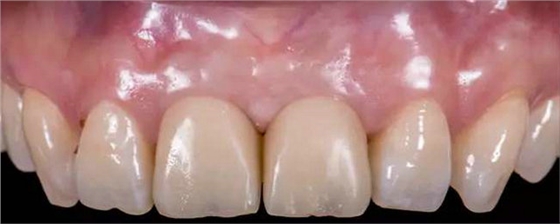

治療效果

修復(fù)前

修復(fù)后

本病例中通過(guò)對(duì)患者修復(fù)體佩戴后的舌側(cè)、頰側(cè)、左側(cè)、右側(cè)以及微笑照的采集,充分展示修復(fù)體在口內(nèi)的佩戴情況,可以看到無(wú)論顏色還是與鄰牙的匹配適宜度都是非常高,也比較吻合年輕女性對(duì)美觀的要求。同時(shí),通過(guò)術(shù)后多次隨訪及跟蹤患者后期使用狀況,患者也對(duì)修復(fù)效果十分滿意。